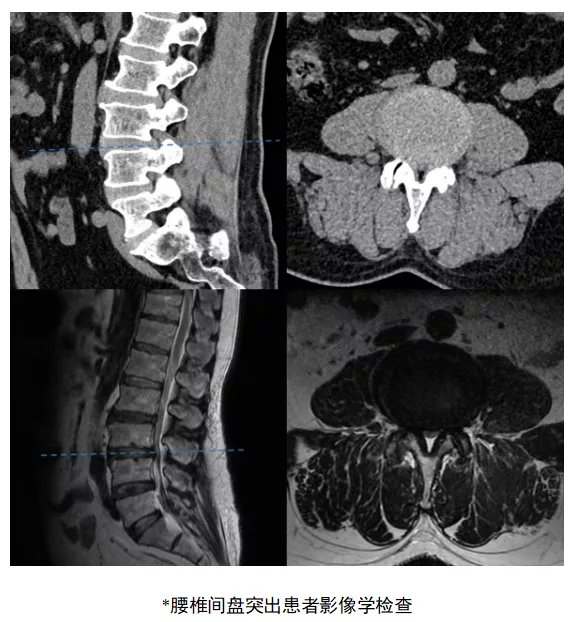

这位来自东北的刘先生是一位老腰椎间盘突出患者了,5年间反复的腰腿痛折磨已使久病成医的他对于保守治疗失去信心,前段时间甚至出现步行50米就腿痛难忍等症状,严重影响患者日常生活。4月中旬,刘先生来到济南市中心医院脊柱外科病区住院治疗,龚维明主任经过详细的体格检查与影像学评估,确诊为腰3-腰4腰椎间盘突出症、腰椎管狭窄症。脊柱外科龚维明医师团队充分分析了患者的病情并制定了诊疗方案,选择了脊柱微创技术——扩张通道系统下经椎间孔入路后路植骨融合内固定微创手术(mis-TLIF),在“硬币”大小的扩张系统下顺利解除患者的腰椎病变,患者术后第二天即下地活动。

在很多病人的传统印象中,脊柱手术一直是开大刀才能解决的,不到万不得已不会轻易下定决心。但如今的脊柱外科手术早已发生改变,精细化、微创化、个性化已成为脊柱外科手术的特点。龚维明主任介绍说:传统腰椎手术需要广泛剥离肌肉和去除骨质,腰椎后方破坏结构多,患者术后卧床的时间长,容易出现血栓及肺部并发症。mis-TLIF手术作为脊柱外科的常规治疗方案,已广泛应用于脊柱外科腰椎椎管狭窄症、腰椎滑脱症、重度腰椎间盘突出症、腰椎退行性侧弯等腰椎疾病的治疗,年手术量位居省内前列,并取得了良好的效果。术者选择通过通道进行精密操作,在狭窄的操作空间下同时做到既减压又融合,实现双重的治疗效果。